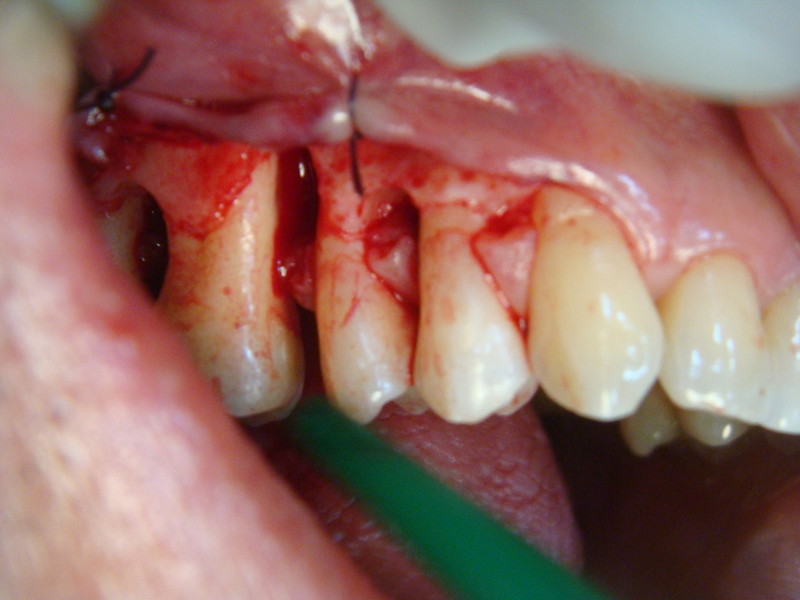

Chirurgia plastica Muco-Gengivale

Rigenerazione difetto parodontale di un canino inferiore con materiale eterologo